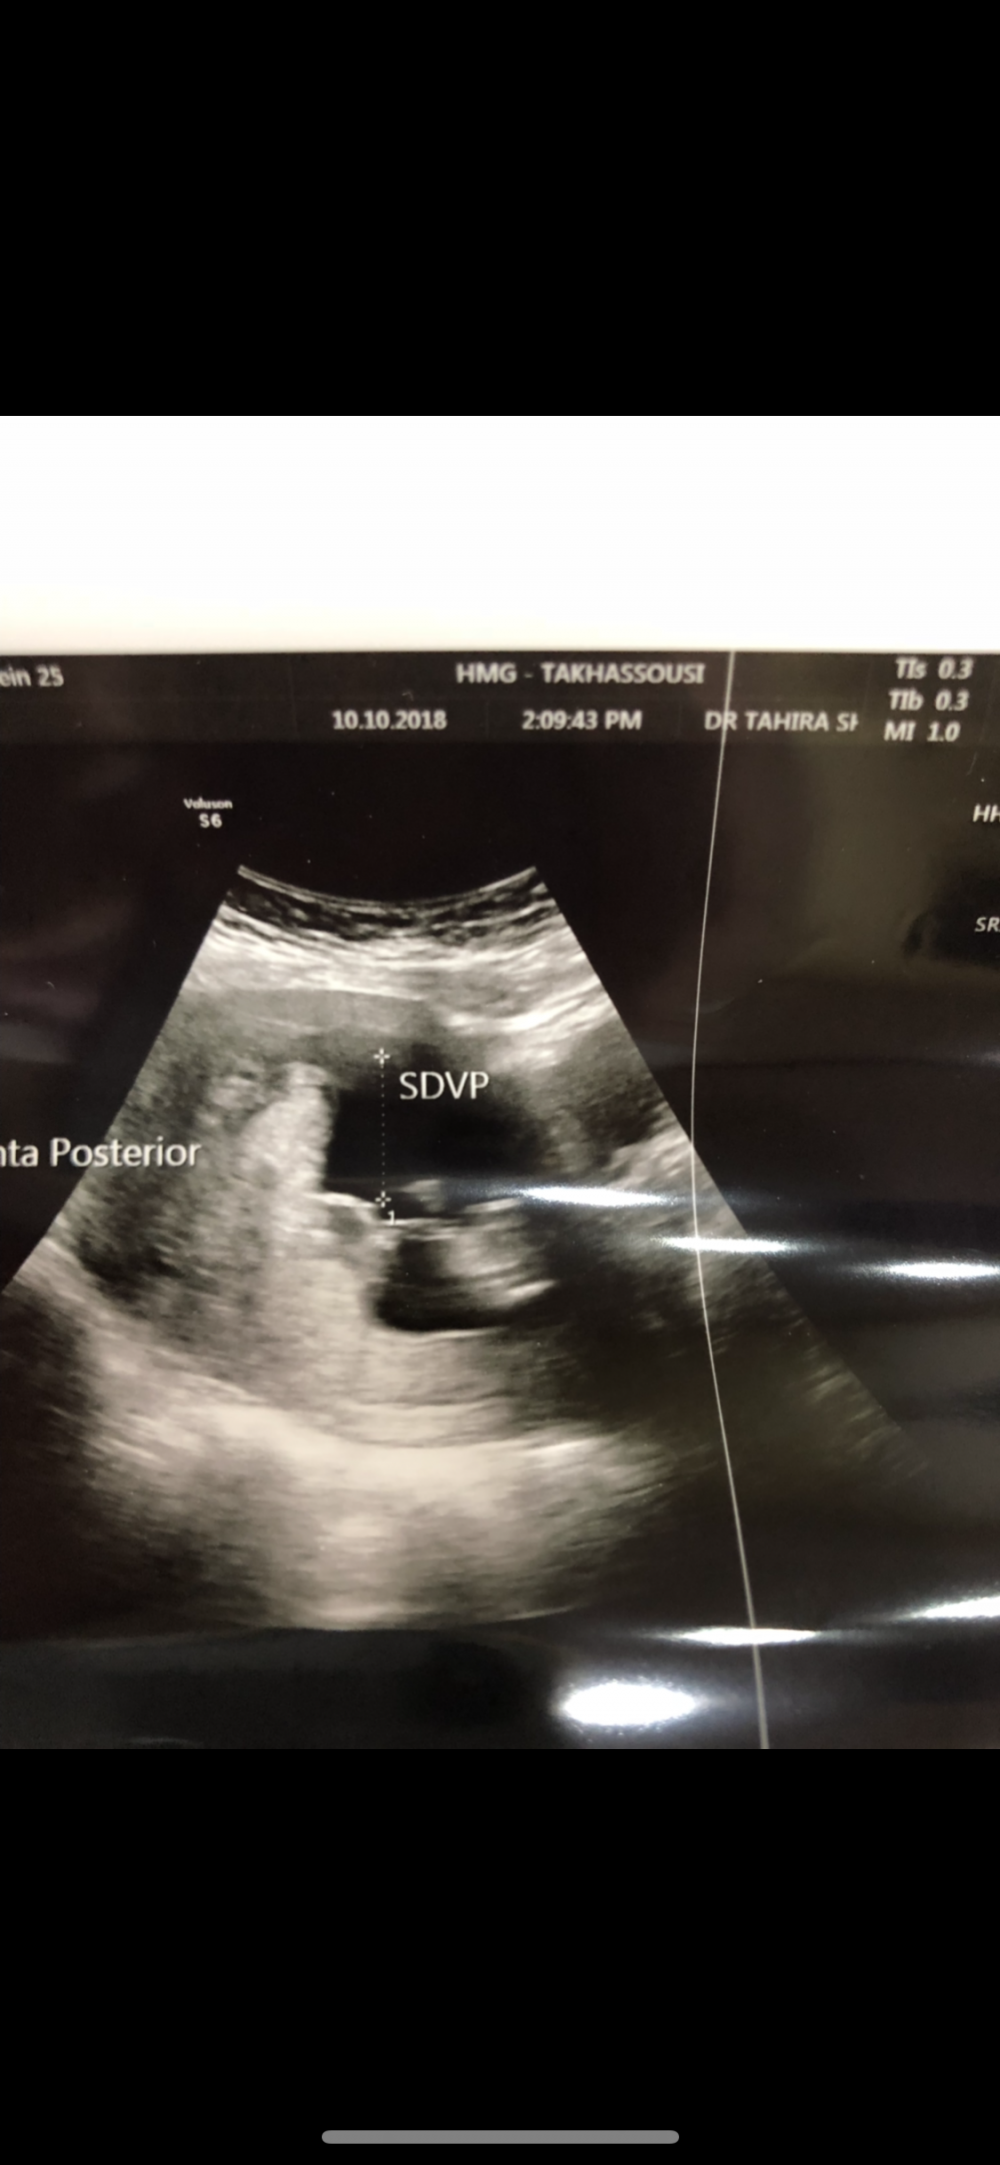

وهذي صورة ثانيه 🌚